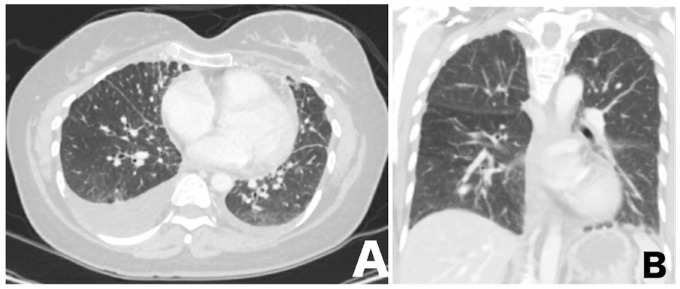

SARS-CoV-2 infection induces myocardiopathy in 19% of severe cases, with a mortality rate of up to 51%. The mainstay of treatment is supportive care, steroids, and tocilizumab (anti-IL-6). This is a case of a 43-year-old woman diagnosed with hormone-positive breast cancer with lung metastasis and pulmonary lymphangitis carcinomatosis (PLC). Her baseline cardiac function was within normal limits. She presented to the emergency department with respiratory distress. Chest CT showed multiple bilateral ground-glass opacities consistent with COVID-19 pneumonia and confirmed by COVID-19-PCR nasal swab. Her condition deteriorated, and she was urgently admitted to the intensive care unit with evidence of a cytokine storm. She was started on tocilizumab, dexamethasone, and meropenem. Echocardiogram (echo) showed a severely reduced ejection fraction with severe global hypokinesis. A second dose of tocilizumab was given, and the dexamethasone dose was increased. Fortunately, the patient had significant clinical and biochemical improvement and regained her normal cardiac function. In conclusion, dexamethasone and tocilizumab could be promising aids in treating cardiomyopathy secondary to SARS-CoV-2 infection.

Abstract Image